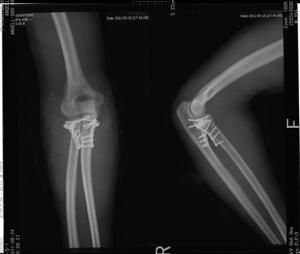

處理方式以往對肘關節“恐怖三聯征”多採取保守治療,一般很難維持肘關節穩定性並有再脫位的傾向,目前學者們多主張採取積極的手術治療。手術治療策略有恢復尺骨冠狀突穩定性、通過橈骨頭骨折內固定或金屬假體置換以恢復外側柱穩定性、修復外側副韌帶及相關結構及必要時修補內側副韌帶或套用可活動鉸鏈式外固定支架輔助固定以利於早期活動。

手術2004年Pugh等提出了治療肘關節三聯征的手術規範。2005年McKee等詳細介紹了手術技巧。方法是採用肘外側入路,由深至淺依次修復下列結構:冠突骨折→前關節囊→橈骨頭骨折→外側副韌帶→伸肌總腱起點。冠突骨折復位後採用空心螺釘固定,骨片太小者採用“拉索”縫合固定;橈骨頭骨折復位後採用空心螺釘、Herbert釘固定,伴有橈骨頸骨折者採用微型鋼板支持固定,只有橈骨頭嚴重粉碎無法固定時,才考慮切除並金屬橈骨頭假體置換,禁忌單純切除橈骨頭。經外側入路修復之後,術中檢查肘關節的穩定性,特別注意在屈伸肘關節20~130°時有無後脫位或後外側半脫位。不穩定在肘伸直和前臂鏇後位時更容易查出。如果此時發現有不穩定,則再作內側切口修復肘內側副韌帶,或使用絞鏈外固定支架。但作者認為單純肘關節外翻不穩定不是修復內側結構的指證。Pugh等報告了36例(36肘)患者,男22例,女14例,平均41.4歲。肘關節三聯征的具體表現為: